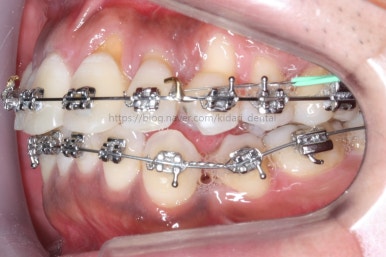

치료 1년 째의 모습입니다.

앞선 모습과 큰 차이가 없는 듯 하죠?

다른 치아는 어떻게 보면 움직임을 멈춘 상태입니다. 오로지 치료는 화살표 치아를 움직이는데 온 힘을 쏟는 중이에요. 이 치아가 제 위치를 잡아야 남아 있는 틈을 모으든 교합을 맞추든 다음 진도를 나갈 수 있기 때문이지요.

치료 1년 5개월째의 모습입니다.

작은 어금니가 어느 정도 올라왔다고 판단되어, 본격적으로 틈을 줄이기 시작했어요.

오른쪽 아래 맨 뒤어금니는 예후가 불량하여 살려쓰기 힘들다고 판단이 되어 발치했어요. 추후에 임플란트를 하셔야 합니다.